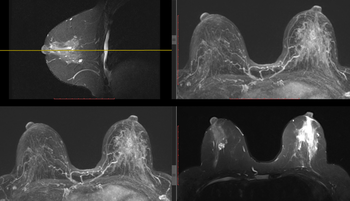

Le Service assure également la prise en charge chirurgicale de l’ensemble des pathologies mammaires de l’institution. Cela inclut les tumeurs bénignes et malignes du sein, les mastectomies simples ou associées à une reconstruction mammaire immédiate, ainsi que la reconstruction différée après traitement.

Nos spécialistes prennent en charge également les patientes présentant un risque élevé de développer un cancer du sein dans le cadre d’une prédisposition génétique, en collaboration avec les autres services impliqués. À ce jour, la majorité des cas de cancer du sein sont traités par notre Service, garantissant une continuité et une expertise spécifiques en chirurgie sénologique.